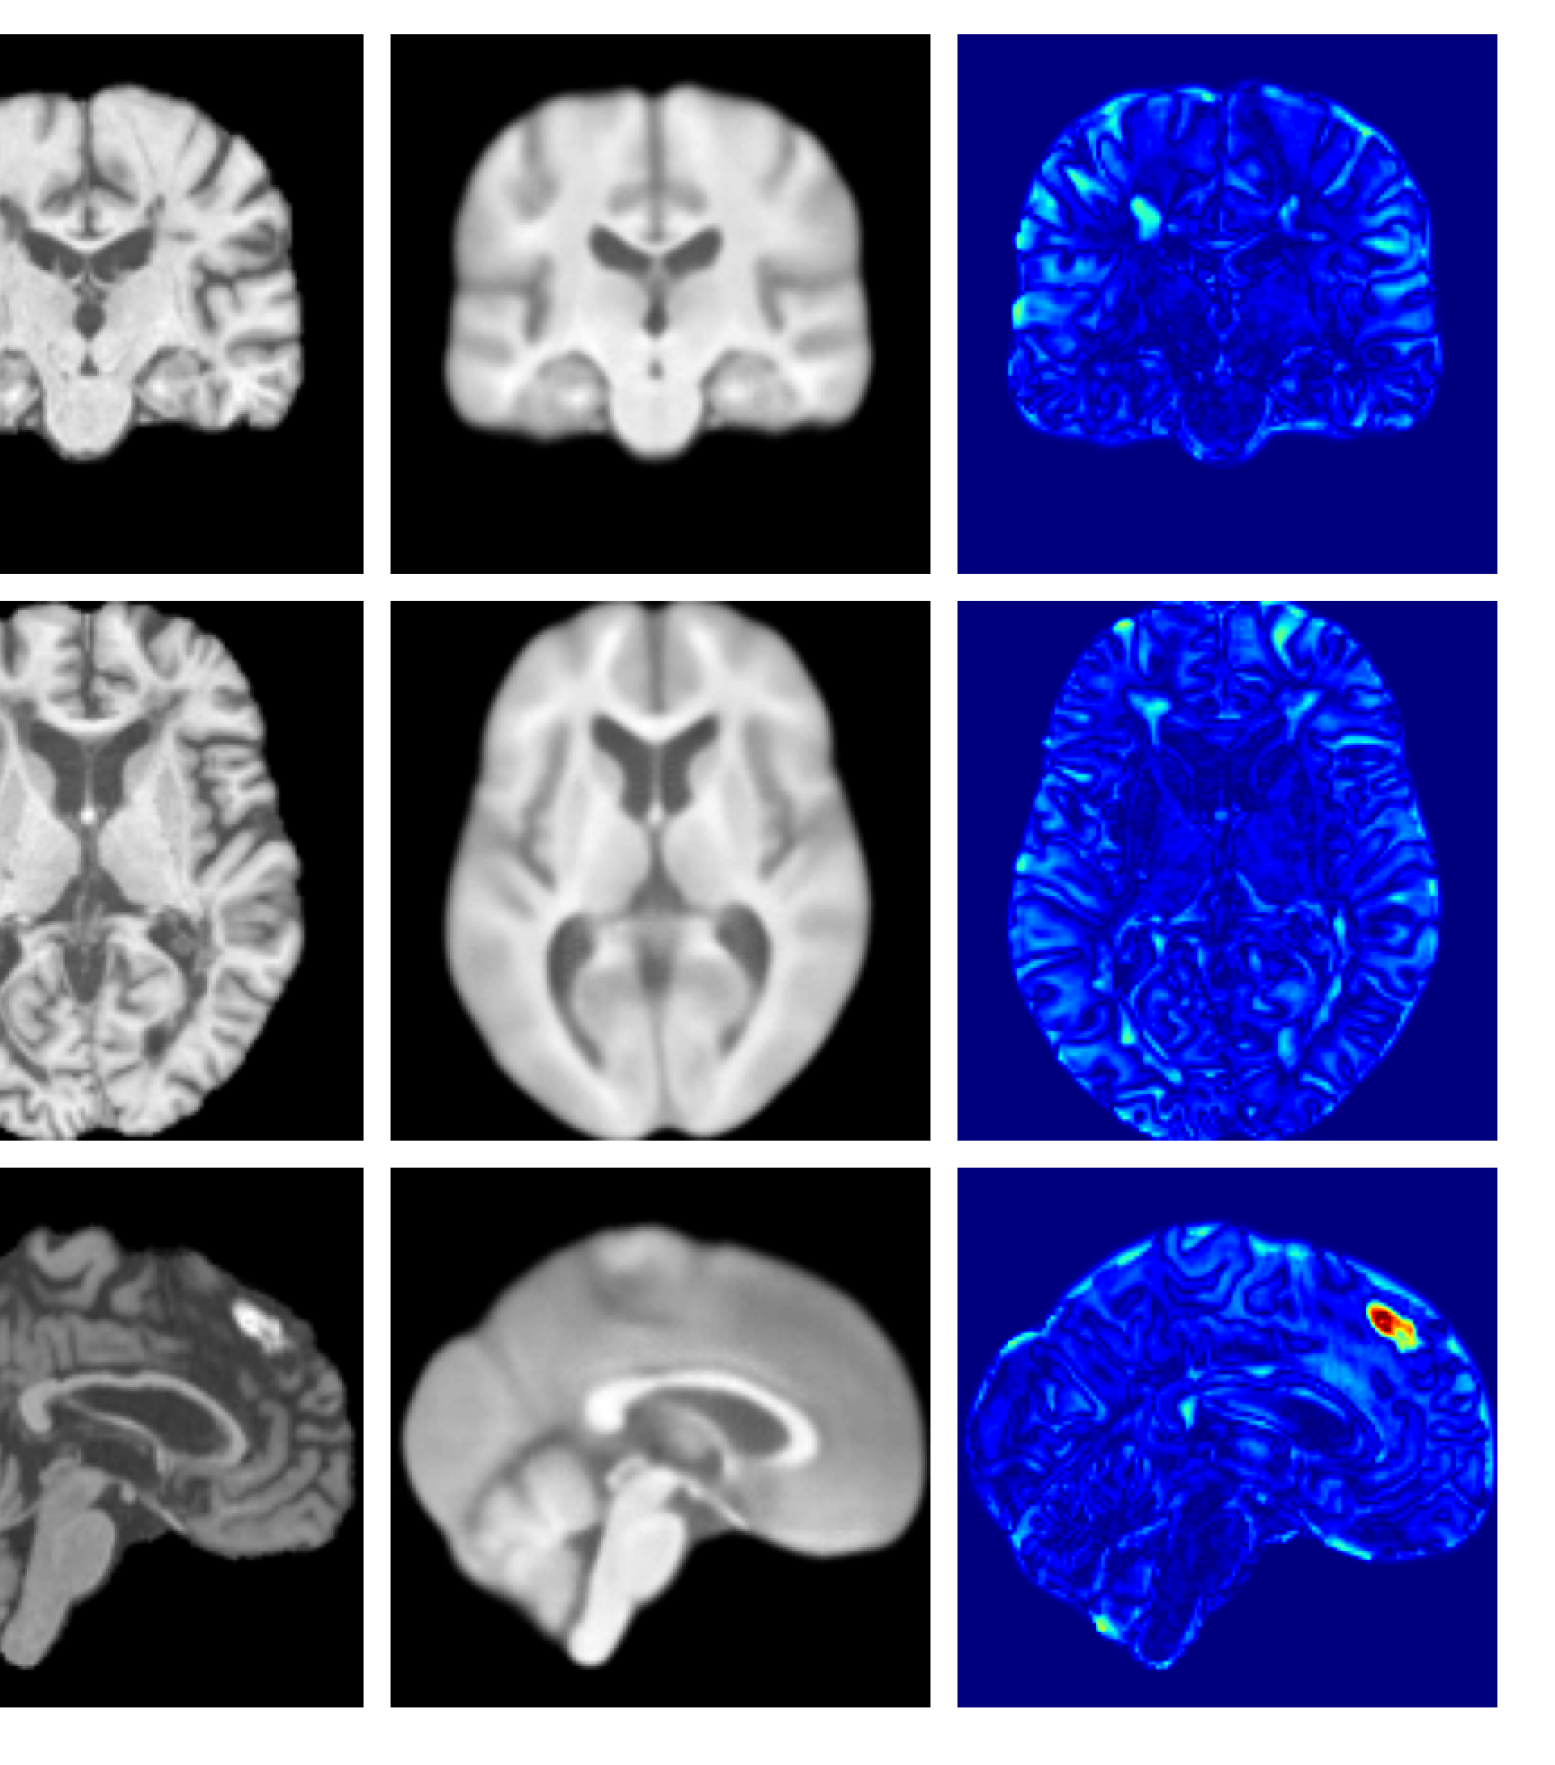

Figures 8 and 9 are enlarged versions of Figures 3 and 4 respectively, with the latter now including results from all compared methods. Figure 10 provides example reconstructions and anomaly maps for an AD subject from the ADNI disease cohort.

Refer to caption

(a) Input

Figure 10: Example reconstructions and anomaly maps for an AD sample from the disease cohort of the ADNI dataset. We expect to see some inpainting of atrophied tissue whilst retaining the defining characteristics of the individual sample.